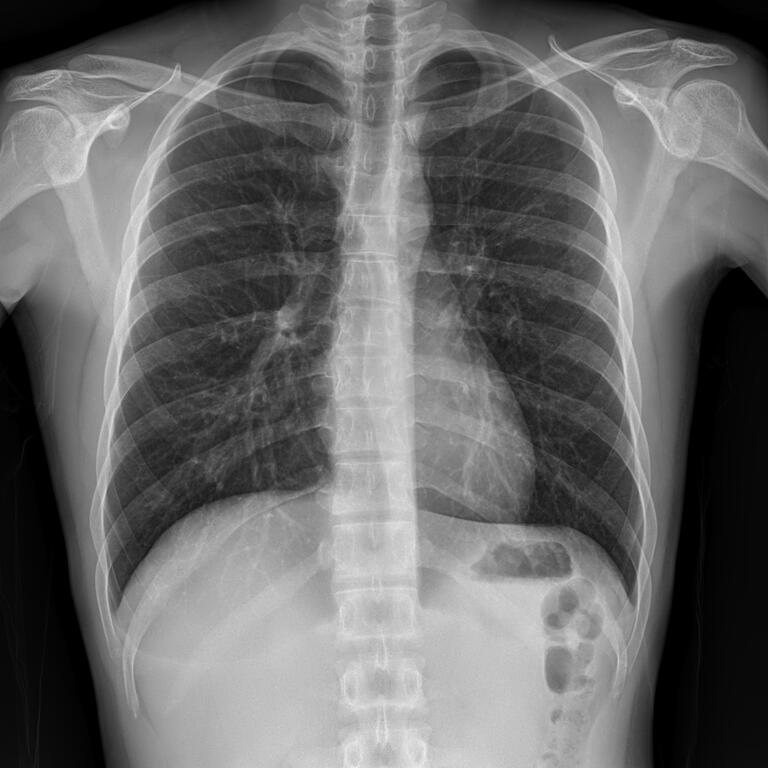

План обследования на туберкулез на 2023 год